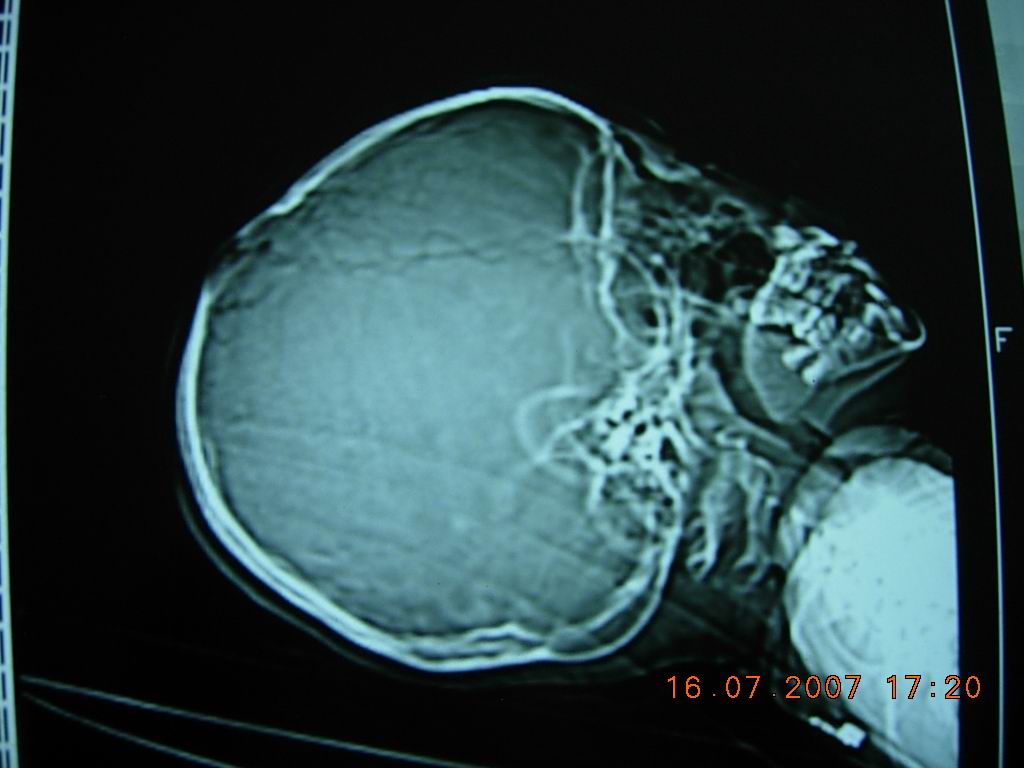

10岁女孩,家人十天前无意中发现顶部一硬的骨性突起,大小约3cm*4cm,无阳性临床症状。头颅ct如图所示。右顶骨内板骨质吸收消失,局部板障欠清,外板变薄呈局限性的轻度隆起,颅内脑实质未见异常征象。头皮软组织未见明显肿胀。考虑颅骨发育异常可能性大。请各位高人及同道指导,发表高见。

典型的顶骨大蛛网膜颗粒压迹。详见《中华放射学杂志》1994年第9期

chinese journal of radiology 起止页码:611-613国际标准刊号:issn 1005-1201国内统一刊号:cn 11-2149顶骨大蛛网膜颗粒迹:(附100例分析)

笔者分析100例顶骨大蛛网膜颗粒压迹,总发生率为19.8%,头颅正位片呈卵圆形或圆形骨质密度减低区,直径大于10mm,常位于顶前1/3区,对称分布于中线两侧、侧位或切线位呈弧形隆起,很象病理改变。

本例为右侧顶骨单发。

将上述杂志讨论部分简述如下:蛛网膜颗粒压迹大家已熟知,常位于中线两侧25-30mm 区内,直径2-4mm,圆或卵圆形骨质密度减低区,有的有引流静脉相连。

顶骨大于10mm的蛛网膜颗粒压迹,尚无专题报道,在临床实践中,常被误诊为病理改变,熟悉其特点,有利于鉴别诊断,避免不必要的检查。根据本组分析,特点如下;1、大的蛛网膜颗粒压迹以20岁以前多见,常因偶尔发现顶骨局限性隆起而就诊。2、头颅正位片呈卵圆形或圆形骨质密度减低区,对称分布于中线两侧,边缘清楚,上半部较硬,双侧大小各异。3、侧位片成弧形隆起,颅板变薄,重者内外板及板障分界不清,仅呈一致密弧线。4、弧形隆起常在冠状缝后方,极少跨越冠状缝。5、隆起的头皮组织正常。6、临近可见小蛛网膜颗粒压迹,但无异常血管沟。

正位片骨质密度减低,似颅骨病变,但切线位和侧位呈典型的颅板内压性改变,不同于颅骨嗜酸性肉芽肿,皮样或表皮样囊肿等病变所致的颅骨缺损,后者病变来源于板障,切线位片颅骨内外板分别向内外膨隆或翘起。脑凸面胶质瘤,脑外蛛网膜囊肿或硬膜内或外慢性血肿或水瘤都可压迫或侵蚀颅板,使其变薄,隆起或缺损,但大的蛛网膜颗粒压迹的部位和双侧对称分布,不同于前者。先天性顶孔很像顶骨大蛛网膜颗粒压迹,但前者是先天异常,位于顶后1/3区,双侧对称,大小各异,直径偶达数厘米,有导静脉通过,可触及骨缺损和波动。正位片呈圆或卵圆形缺损区,边缘锐利,无硬化,侧位或切线位呈局部颅板缺损,不是弧形隆起。

分析:本例侧位定位像表现典型,ct显示右侧改变,与报道者双侧多对称不同,但上述其他病变均可排除,诊断还是成立的。敬佩解放军总医院陈巨坤等对此征象的研究,到其发表时尚无专题报道。我94年就拜读此文,并应用于实践,注意观察,此征确实不少见。我认为应该属于正常变异。(发生率20%左右)